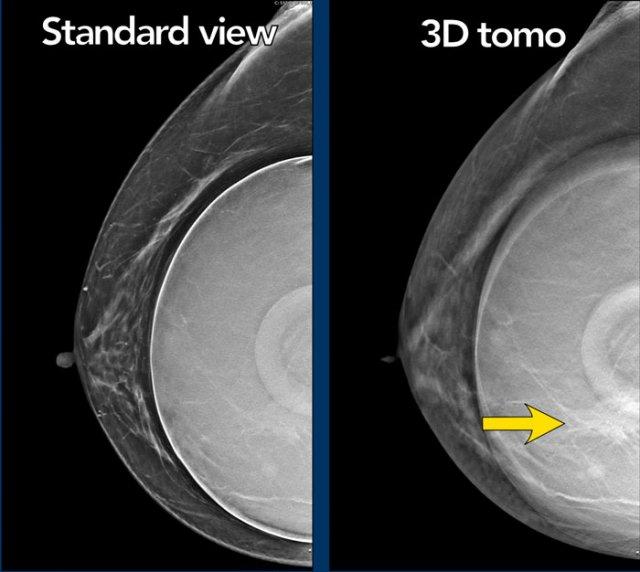

Một ví dụ khác về giá trị của chụp cắt lớp tổng hợp.

Khối u được thấy rõ nhất trên hình ảnh cắt lớp.